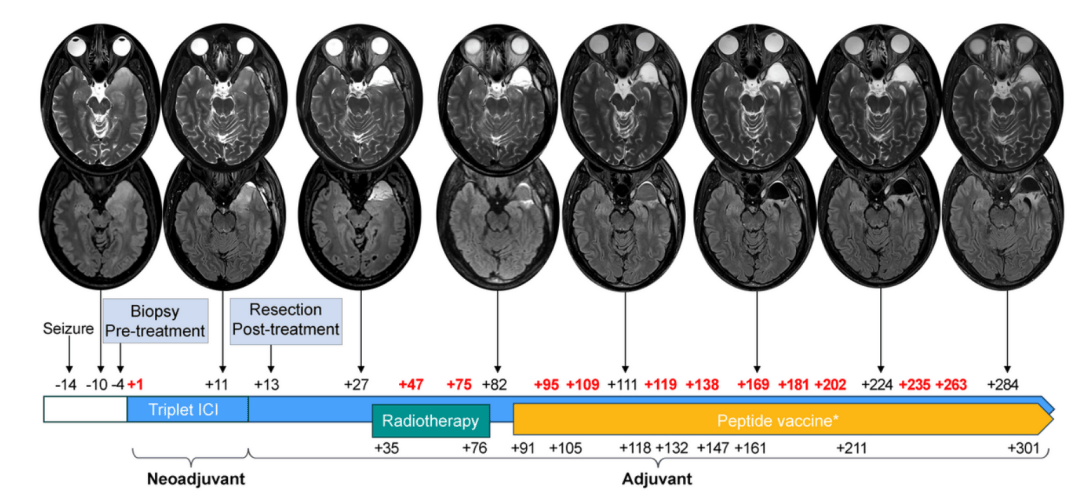

活檢明確病理後,理查德先做了1個週期的三聯免疫檢查點阻斷(ICI)治療。12天后,完成GBM切除術。再接着,他做了局部放療,又經歷單藥免疫治療、糾正免疫不良反應後繼續接受多聯ICI,以及4次個體化腫瘤疫苗接種。

圖源/Nature Portfolio

結果如他所料。理查德的腫瘤屬WHO Ⅳ級、IDH野生型、MGMT未甲基化,幾乎是GBM中預後最差的一類。但也有好消息:經過三聯ICI後,組織內多處免疫細胞都有10倍以上增加,提示腫瘤微環境明顯改變!

當地時間2024年5月14日,理查德通過社交媒體宣佈,治療近1年後,自己病情穩定、未檢出GBM復發跡象。他表示,自己留取了寶貴的生物樣本,包括新輔助治療前後的腦腫瘤樣本,整個治療過程中的血、糞樣本,以及腦脊液樣本等,未來會進行更詳細的轉化研究。

2024年3月19日,理查德·斯科萊爾在個人社交媒體發佈了治療10個月後的腦部複查結果。/Richard Scolyer